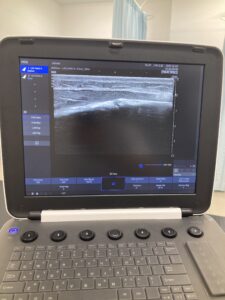

次にエコーで患部をみます。

★腓骨疲労骨折のエコー写真↓

真ん中に亀裂が入っているようにみえます。

これが疲労骨折です。